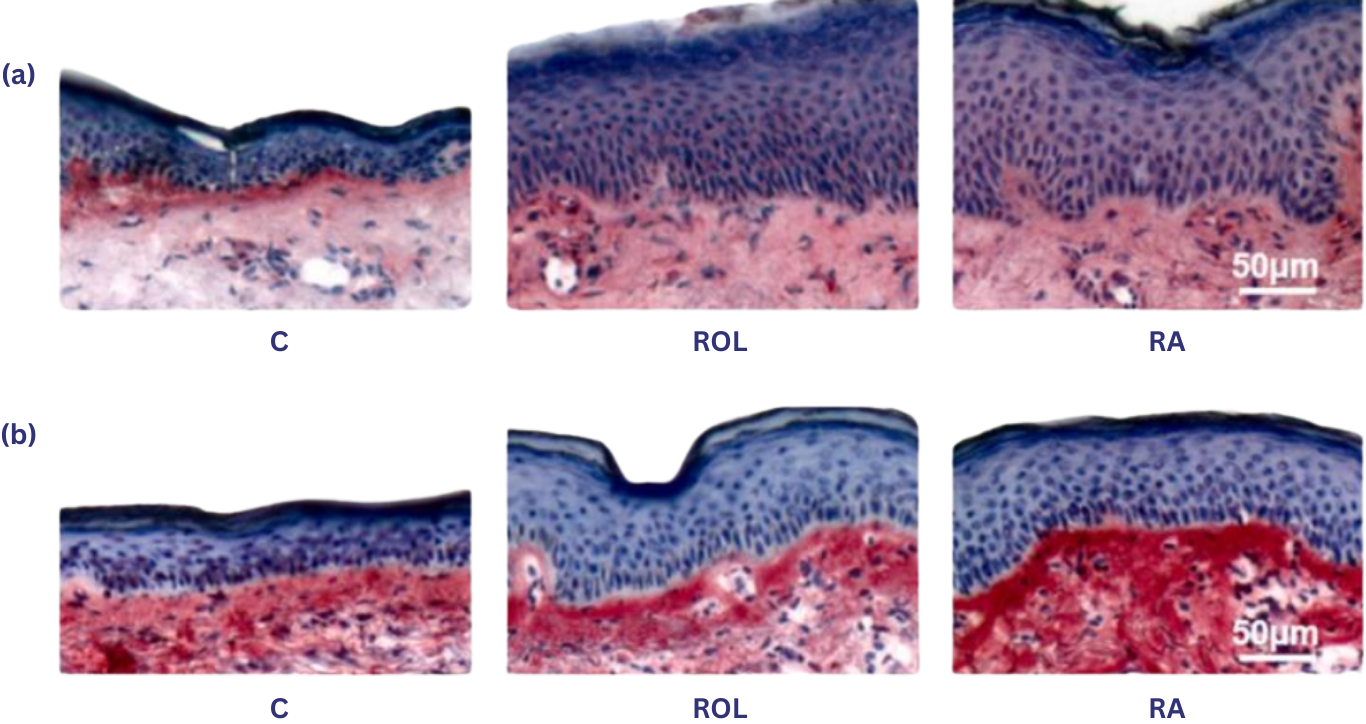

increase in epidermal thickness

Retinol and retinoic acid treatments increased epidermal thickness by 46.28% and 78.79%, respectively, consistent with H&E-stained sample observations. (pp. 15–16)